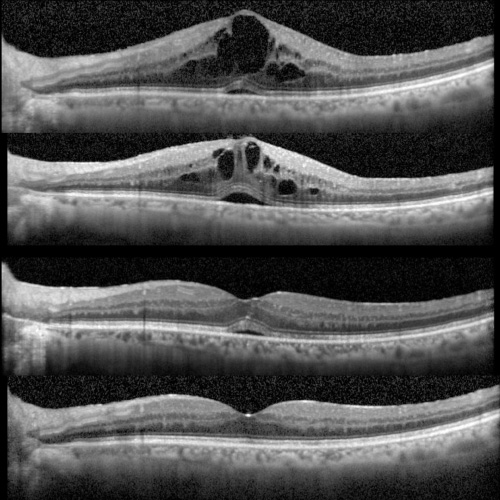

Diagnostica el despegamiento de la neuroretina del Epitelio Pigmentario de la Retina

Estudia la pérdida de continuidad de la neuroretina en la mácula

Análisis del desprendimiento seroso de la retina en la mácula

Examina la superficie retinal y los cambios producidos por la interfase vitreoretinal

Evalua las alteraciones producido por efecto de las fuerzas de tracción de la interfase vitreoretinal